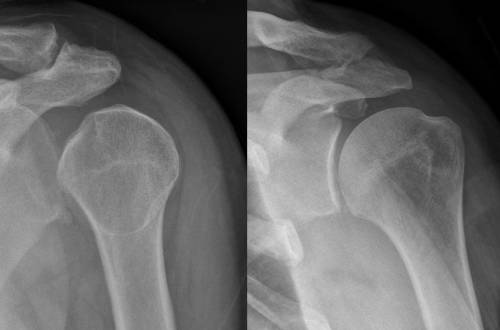

Outdoor Hazards: Dislocated Shoulder in the Backcountry The shoulder is the most mobile joint in the body – and the most likely to dislocate. What would you do if you dislocated a… Written by Steve Graepel January 17, 2018